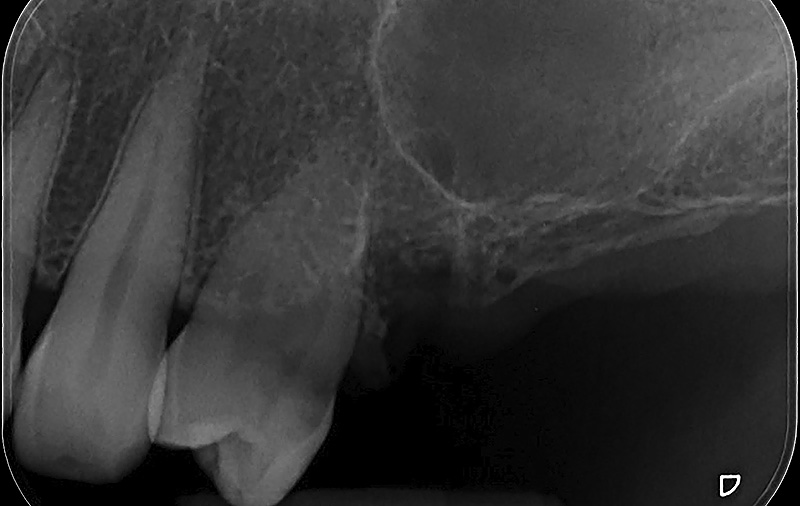

PREMESSA: in seguito all’estrazione dell’incisivo laterale superiore di destra, resasi necessaria per cause batteriche, si decide di affrontare il caso con il posizionamento di un impianto in sostituzione dell’elemento mancante dopo guarigione del sito infetto. Con tecniche rigenerative sia dei tessuti ossei mancanti a causa dell’infezione pregressa, sia dei tessuti gengivali che appaiono inizialmente troppo spostati in alto, si ripristina una corretta morfologia delle parabole (contorni) gengivali e delle papille interdentali (triangoli di gengiva tra due denti vicini).